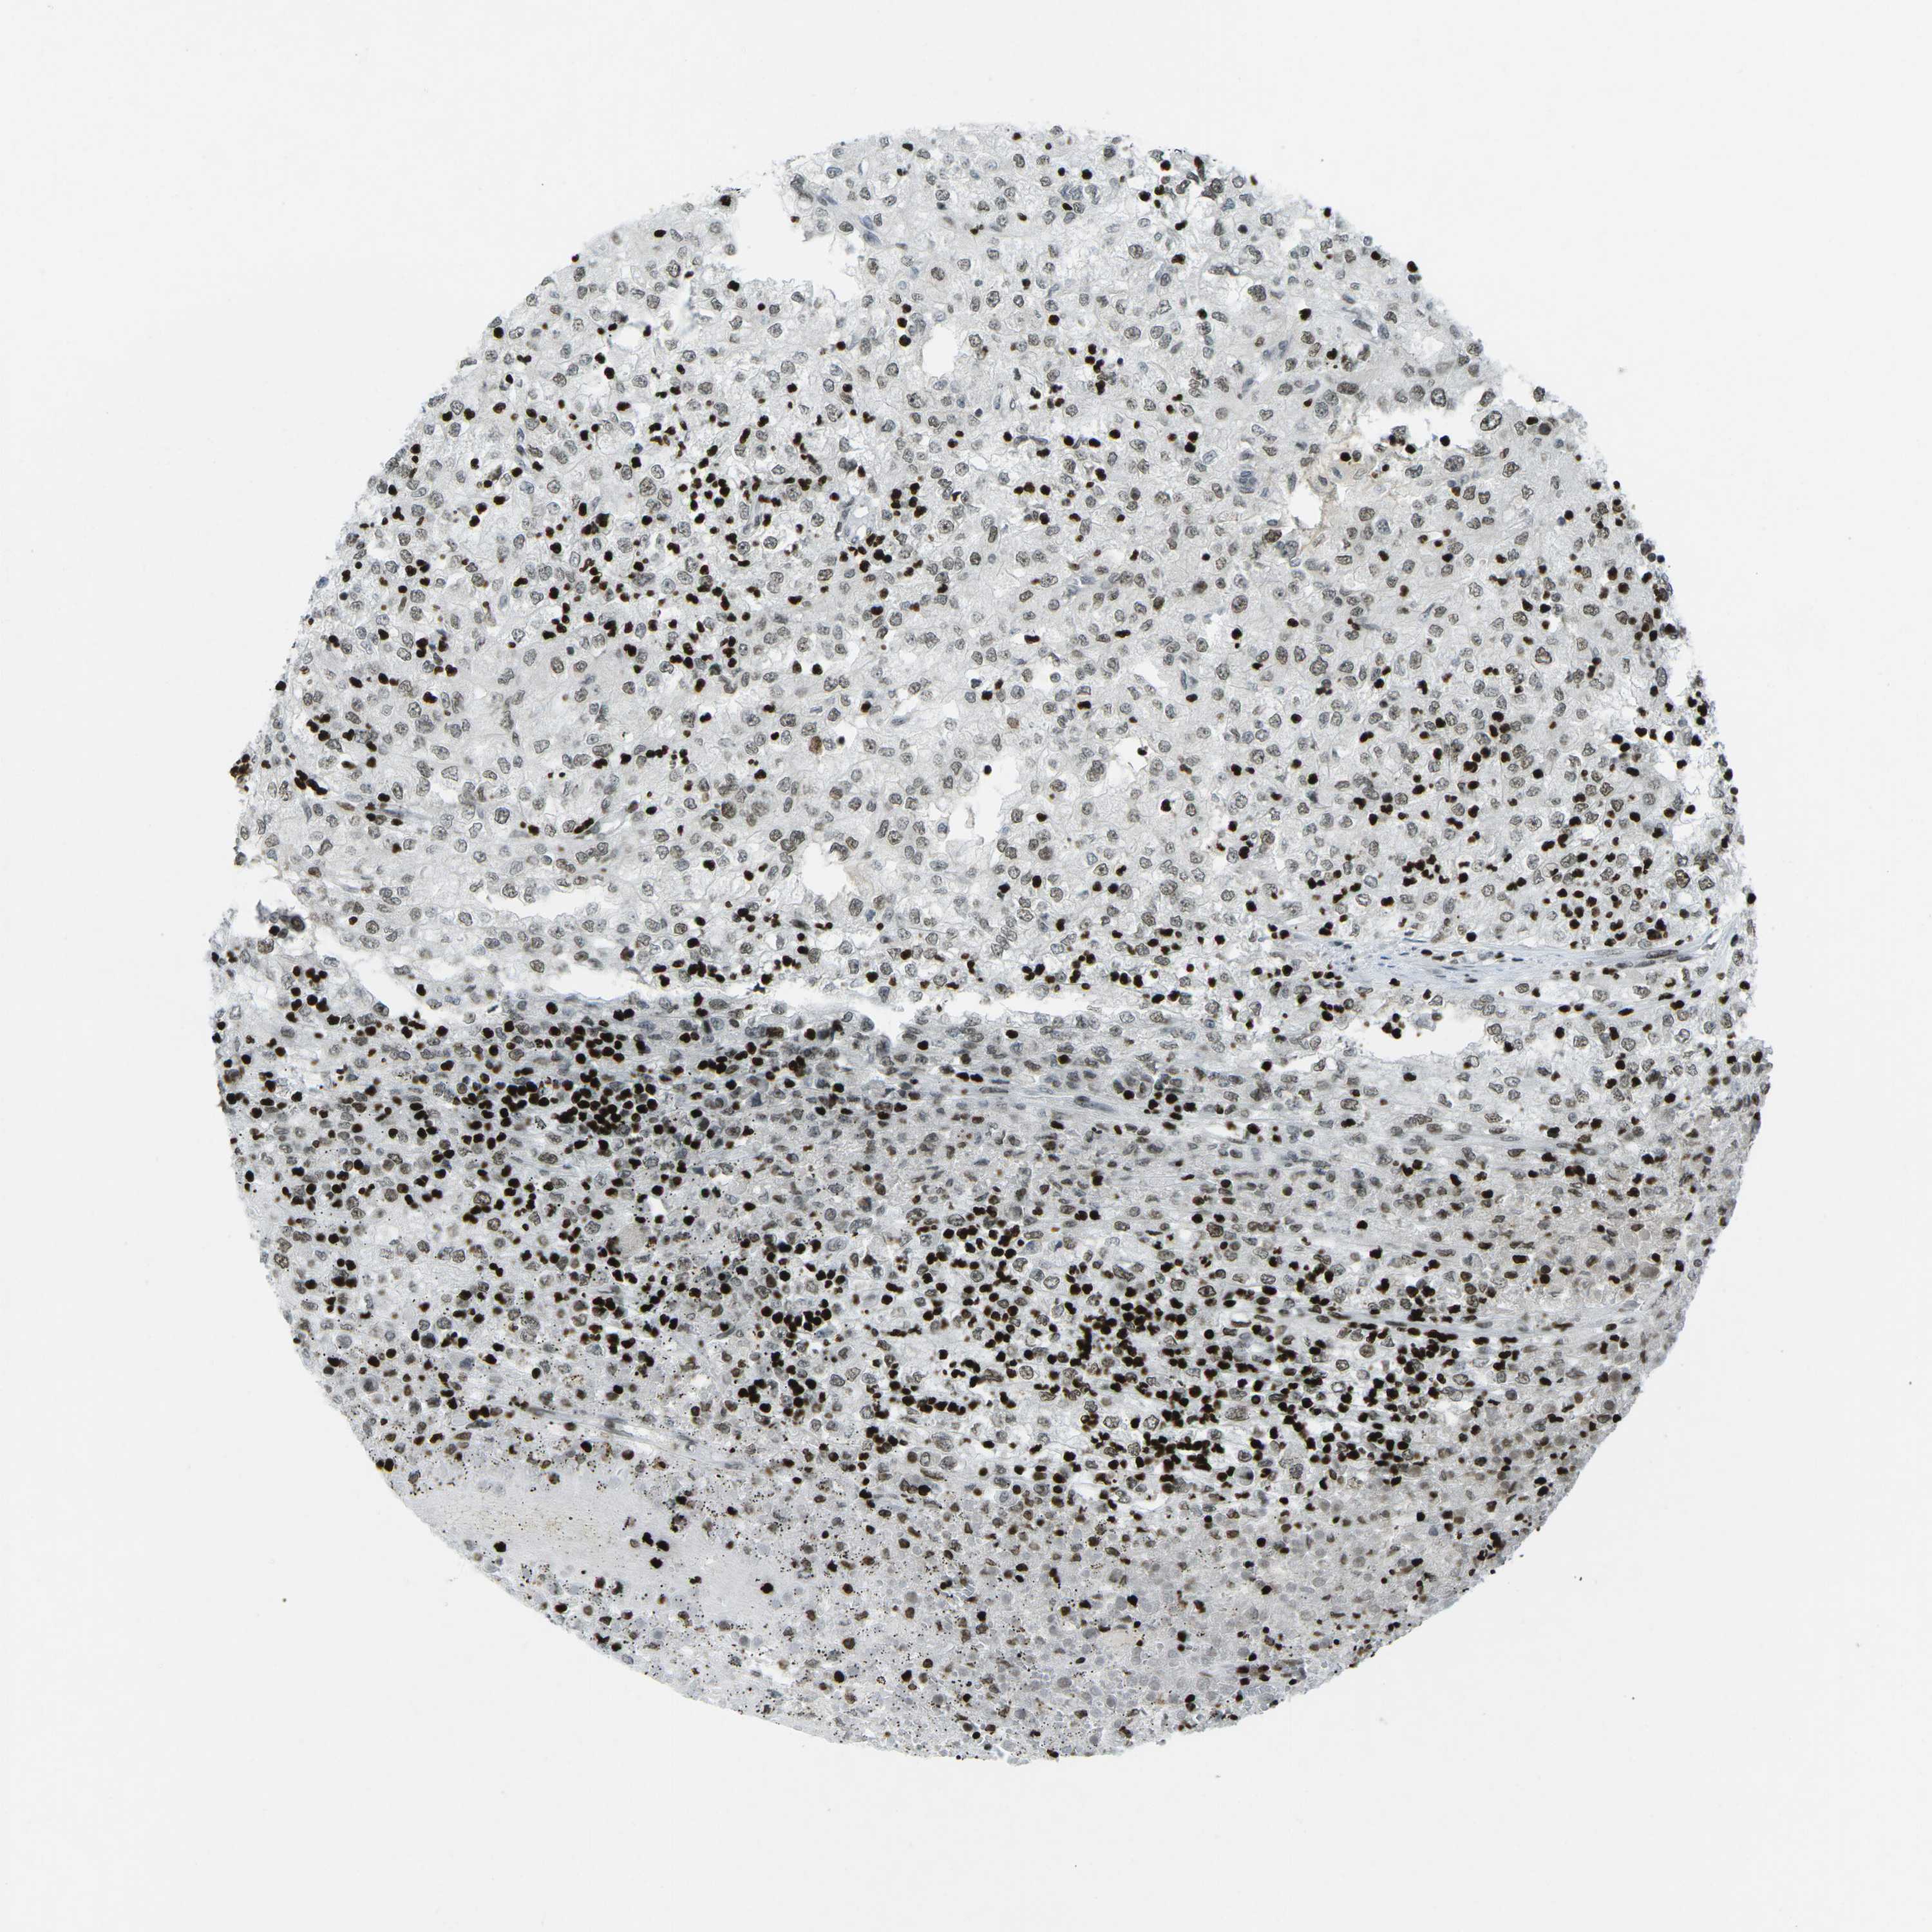

TCGA RNA samplesi

RNA-seq data is reported as average FPKM (number Fragments Per Kilobase of exon per Million reads), generated by the The Cancer Genome Atlas (TCGA) .

Normal distribution across the dataset is visualized with box plots, shown as median and 25th and 75th percentiles. Points are displayed as outliers if they are above or below 1.5 times the interquartile range. FPKM values of the individual samples are presented next to the box plot.

Average pTPM 1.1

Number of samples 100